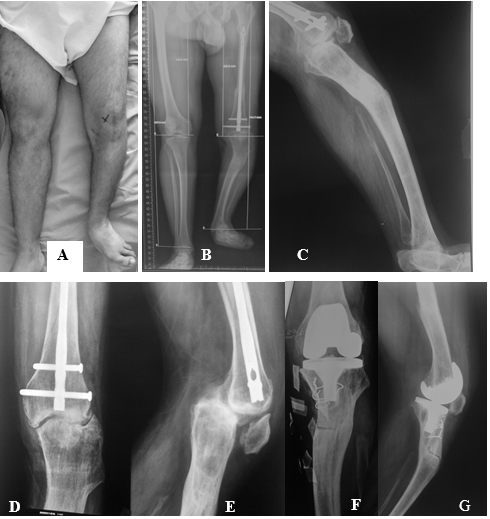

Figura 4: Para la planificación femoral se utiliza una línea de corte distal a 90° del eje mecánico del fémur: a) si afecta a la inserción ligamentaria en los epicóndilos, debe realizarse una osteotomía femoral correctora. b) cuando la línea de corte pasa por debajo de los epicóndilos, basta con los cortes óseos intra articulares para corregir la deformidad. Para la planificación tibial se utiliza la proyección del eje del segmento tibial distal a la deformidad. c) en caso de que el eje pase por dentro de los platillos tibiales, la corrección puede hacerse mediante cortes intra articulares y d) si pasa por fuera, está indicada la osteotomía correctora.